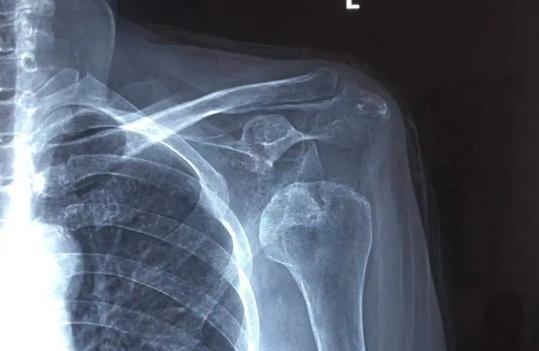

3. 肩关节脱位

肩关节脱位或半脱位是一种可能导致肩膀疼痛的情况。特别是在老年人中,这种情况有时会发生,尤其是当肩部承受外力或过度活动时。

脱位是指关节头从其正常位置移出的情况,而半脱位则是关节头部分脱离正常位置。

在老年人中, 由于肌肉和韧带的老化和减弱 , 肩关节可能更容易发生脱位或半脱位 。

这可能是因为一次突然的运动、扭伤,或者承受了过多的外力,如跌倒时用手支撑等。

当肩关节发生脱位或半脱位时,通常会引起剧烈的疼痛,肩膀可能会变得不稳定,甚至运动时出现异常感觉。

这种情况需要及时就医,医生可能会对关节进行重新定位,然后通过休息、康复锻炼和物理治疗来帮助肩膀康复。